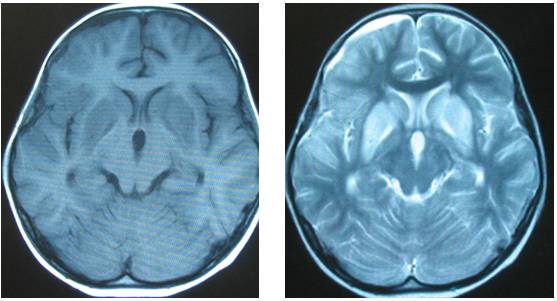

查体:T36.5℃,P102次/分,R24次/分,BP95/65mmHg,身高105 cm,体重18kg。神志清,精神好。颅神经检查未见异常,四肢活动正常,肌张力无增高,无肌震颤。感觉无异常,腱反射正常,病理征阴性。实验室检查:血、尿、便常规及血生化、电解质、肝肾功能均正常。垂体激素正常。头颅MRI检查,提示“鞍上颅咽管瘤”,向上突入第三脑室(图1)。

图1. MRI增强显示鞍上肿瘤,突入三脑室,肿瘤增强明显,部分囊变。